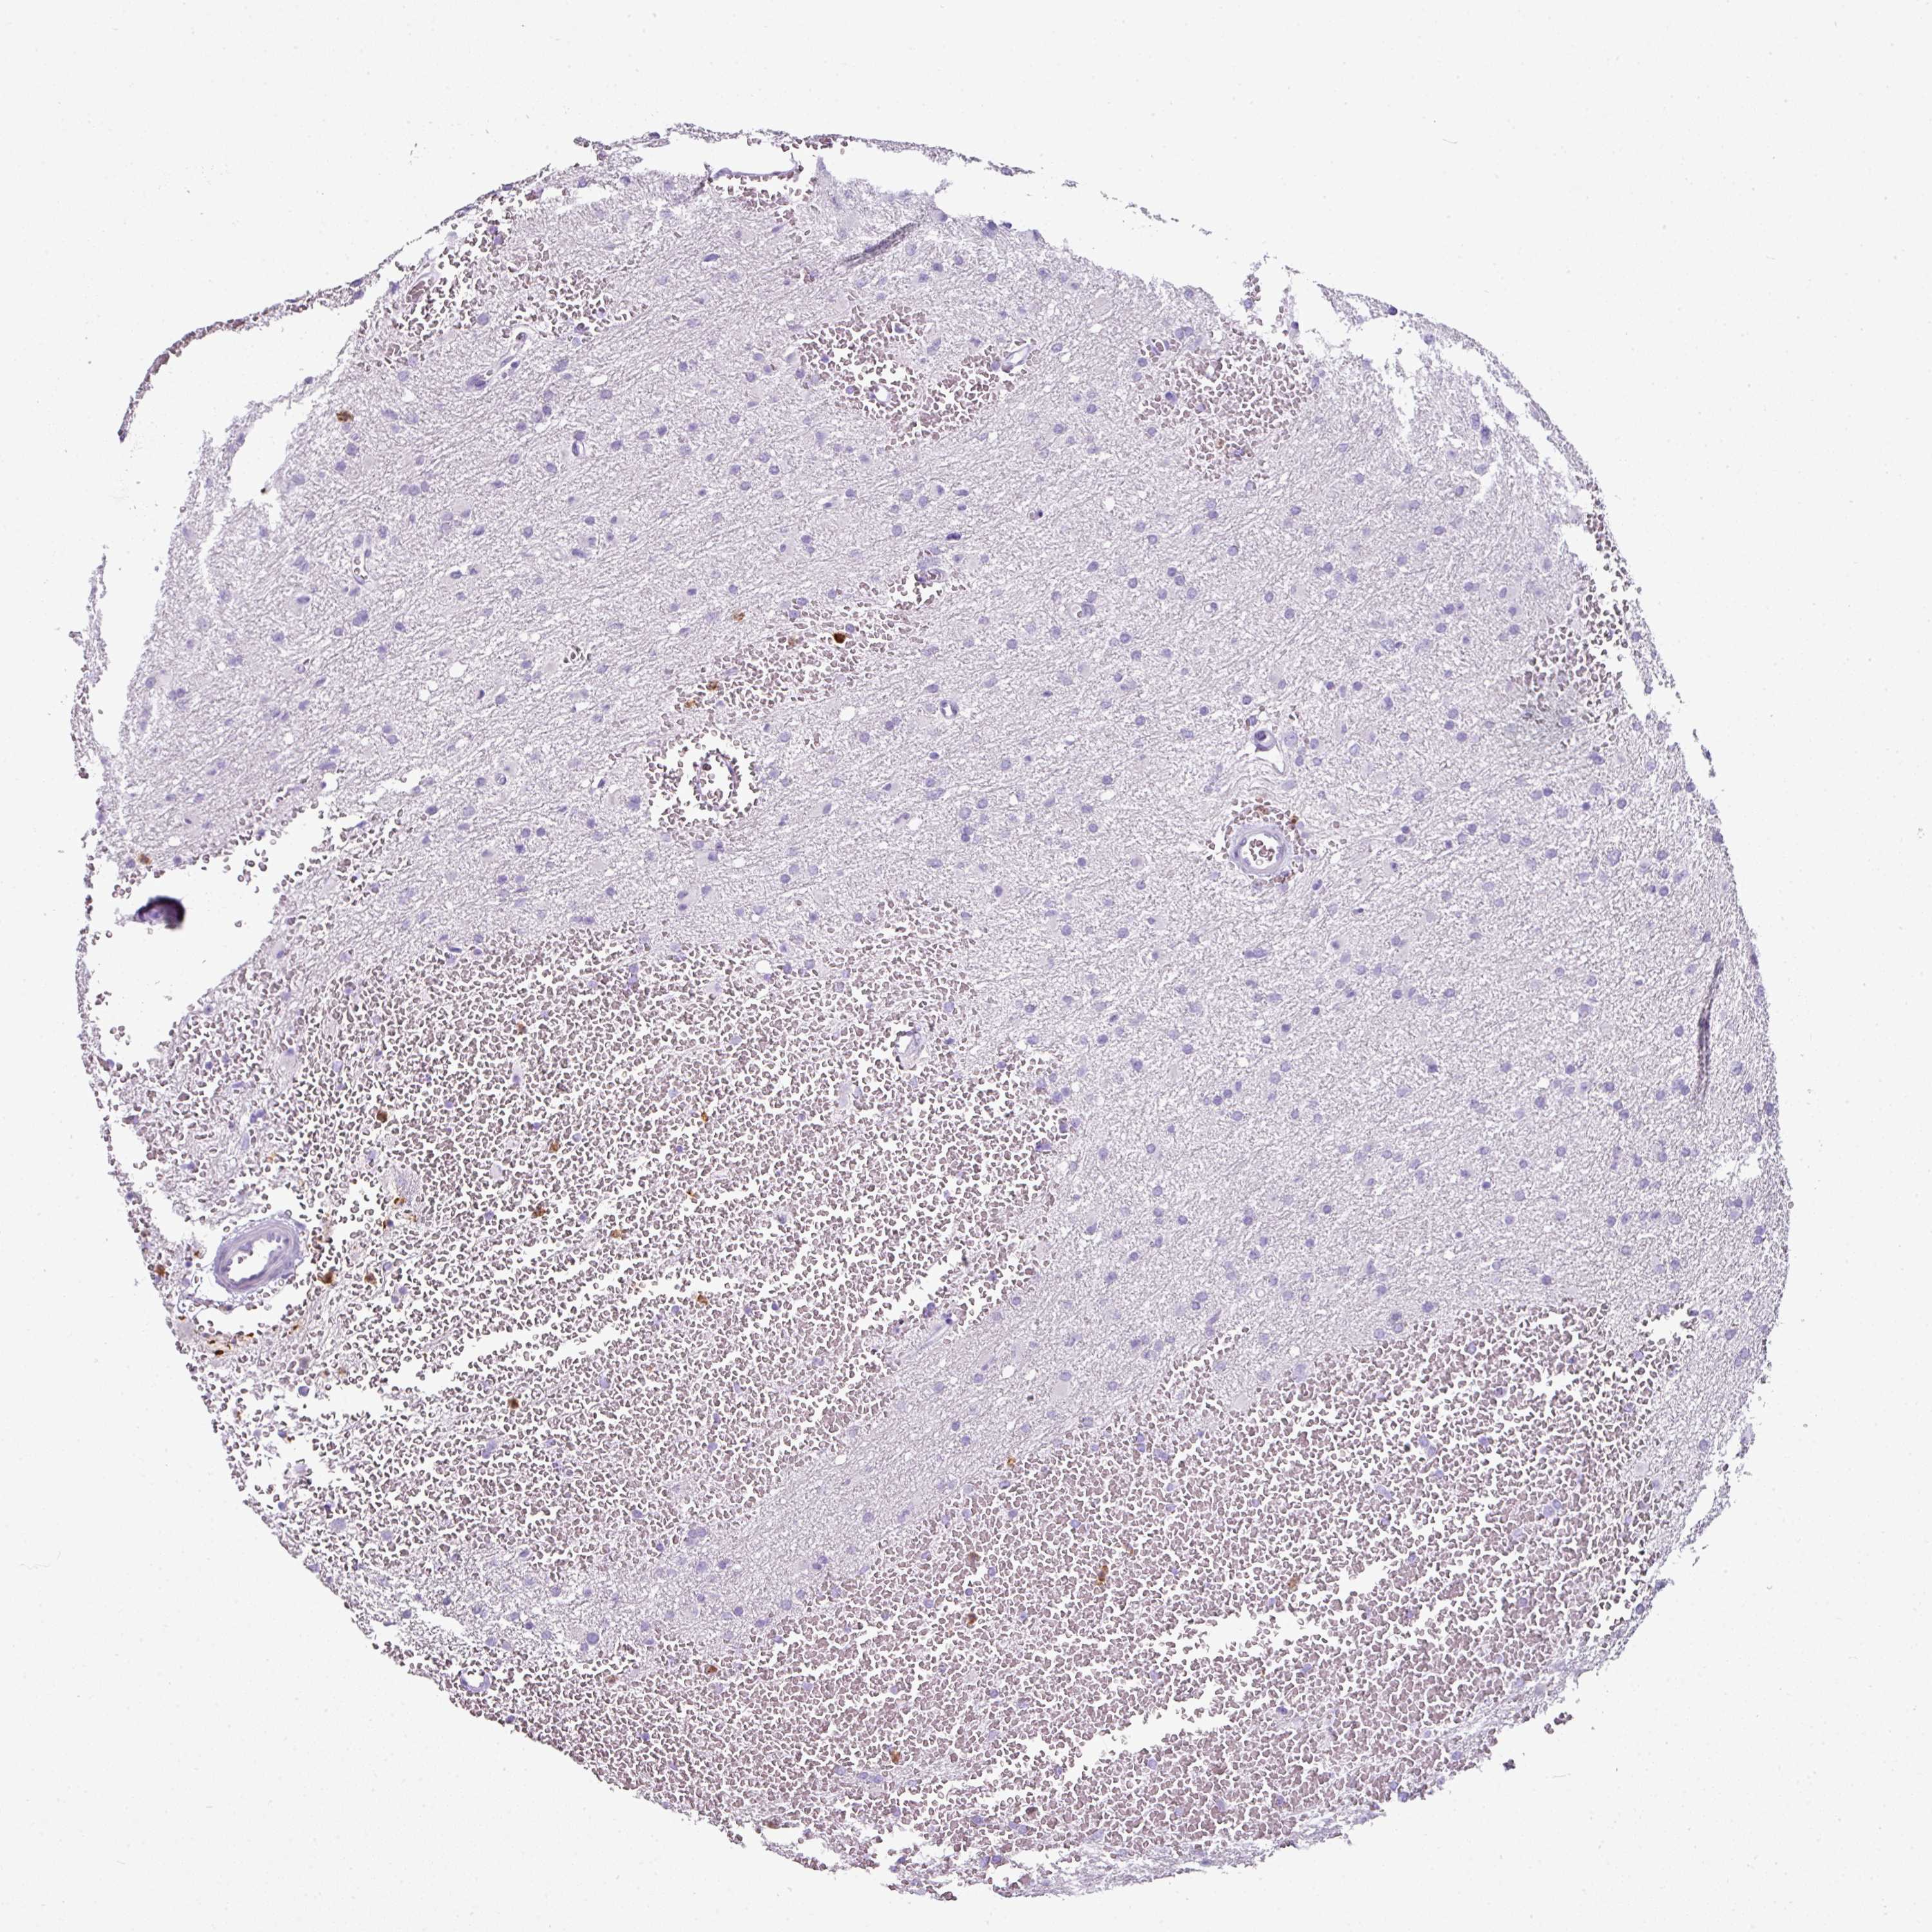

GLIOMA - Protein expressioni

A mouse-over function shows sample information and annotation data. Click on an image to view it in a full screen mode. Samples can be filtered based on level of antibody staining by selecting one or several of the following categories: high, medium, low and not detected. The assay and annotation is described here.

Antibody stainingi

Antibody staining in the annotated cell types in the current human tissue is reported as not detected, low, medium, or high, based on conventional immunohistochemistry profiling in selected tissues. This score is based on the combination of the staining intensity and fraction of stained cells.

Each image is clickable and will lead to virtual microscopy that enables deeper exploration of all samples and also displays staining intensity scores, fraction scores and subcellular localization as well as patient and tissue information for each sample.

Antibody HPA047737

Antibody CAB000110

Staining

High

Medium

Low

Not detected

Intensity

Strong

Moderate

Weak

Negative

Quantity

>75%

75%-25%

<25%

None

Location

Nuclear

Cytoplasmic/membranous

Cytoplasmic/membranous,nuclear

Glioma, malignant, High grade

Glioma, malignant, Low grade